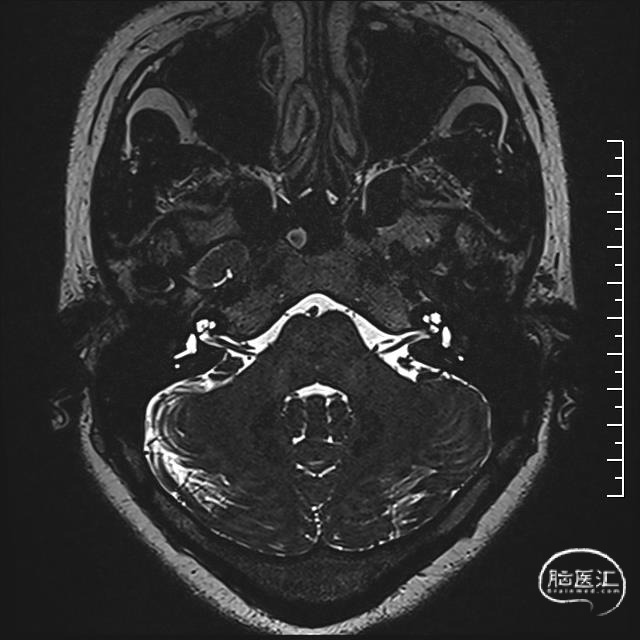

术前MRI:可见面神经REZ区有血管影,但是其信号与动脉信号有区别。同时因后颅窝解剖结构变异,乙状窦位置可能影响CPA区暴露

术前诊断:左侧面肌痉挛,考虑责任血管为:小脑前下动脉或脑干静脉

手术过程:常规侧卧位,乙状窦后发迹内直切口约6cm,星点前下方钻孔后铣刀游离骨瓣,磨钻扩大骨窗达乙状窦后缘,剪开硬脑膜后脑组织饱满释放脑脊液后仍不能显露CPA结构,遂将颅骨进一步磨除显露部分乙状窦,形成扩大乙状窦后入路,同时调整头位和显微镜进一步增加对CPA区的显露,在牵开小脑半球释放桥前池脑脊液后颅压下降脑组织塌陷。从后组颅神经处锐性剪开蛛网膜,暴露REZ区未见明显动脉压迫,只有小脑中脚静脉由桥脑于面听神经之间穿行后进入桥静脉汇入颈静脉孔。向后组颅神经腹侧、桥延沟及内听道处探查无动脉压迫,确认单纯静脉压迫。小块的垫棉小心垫于面神经和静脉之间后电生理提示除眼轮匝肌外其余LSR消失,电生理实时监护下反复调整垫棉位置最终LSR消失。水密缝合硬脑膜,骨瓣复位固定,各层严密缝合。术后患者清醒后面部抽搐未发作,听力正常,无面瘫。